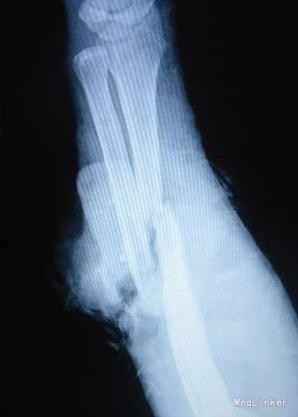

左前臂切割伤:左尺桡骨开放粉碎性骨折,伸肌群断裂,尺侧血管神经束断裂。 手术行清创+尺桡骨骨折内固定+肌腱缝合+尺神经吻合术,术中见尺桡骨断端不整,予修复后钢板内固定,并取人工骨条植骨;术中见指端血供可,指腹饱满,予结扎骨间动脉及尺动、静脉,吻合尺神经。并予伸肌群一一对应缝合。见皮肤张力高,无法完全对合,遗留尺背侧约5.0*4.0厘米创面。术后见指端血供可,毛细血管充盈时间1-2秒。术后第3天患肢肿胀明显,拆除部分缝合线,挤压后有淡黄色脓液流出,伴恶臭,且有伸肌群的坏死;指端血供可。普通培养基做细菌培养及药敏示:溶血性葡萄球菌。每日予甲硝唑+阿米卡星以及双氧水冲洗创面。

术后第7天,皮瓣及伸肌群坏死,创面仍然有少量脓液,无明显恶臭;钢板外露。